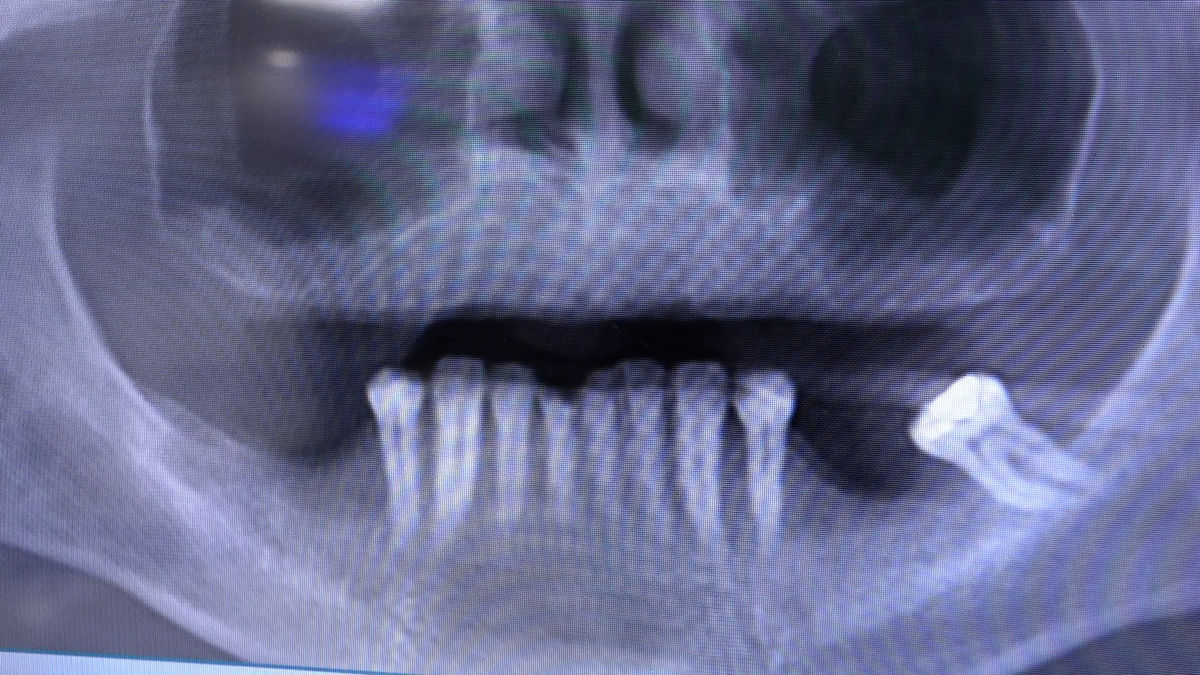

Chirurgia implantologiczna to temat wiodący 5 Sesji X Sezonu Practiculum Implantologii, która się odbyła 23-24 października 2020 roku. Bierze w nim udział 16 adeptów implantologii stomatologicznej. Zabiegi z udziałem Pacjentów jak zwykle poprzedziło omówienie i planowanie, tym bardziej, że zgodnie z planem wykonana została implantacja z wykorzystaniem szablonu chirurgicznego, który przygotowało laboratorium dentystyczne Wiligała Lab. Kursanci wykonywali szereg zabiegów implantologicznych i chirurgicznych oraz regeneracyjnych z zastosowaniem PRF, w tym sinus lift. Przeprowadzali je pod kierunkiem Lidera Umiejętności Implantologicznych dr n.med. Violetty Szycik, która wysoko oceniła wykonanie zabiegów.